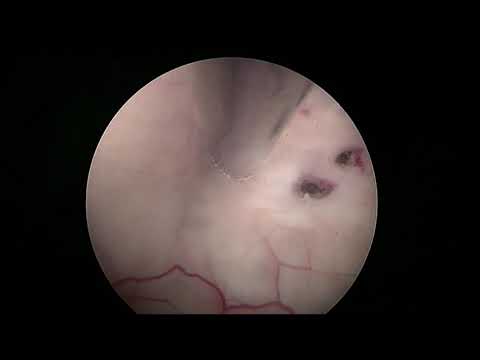

Hellow guys, Welcome to my website, and you are watching Cystocisternostomy of Sylvian Arachnoid Cyst with the LOTTA® Ventriculoscope. and this vIdeo is uploaded by Neurosurgery Greifswald at 2018-11-29T01:55:16-08:00. We are pramote this video only for entertainment and educational perpose only. So, I hop you like our website.